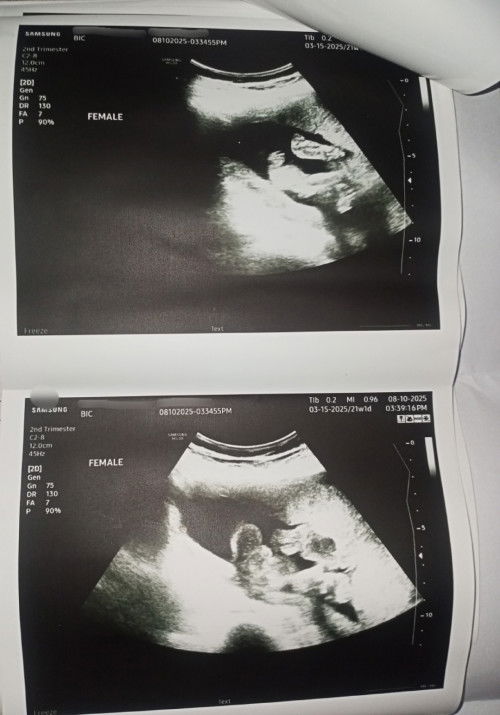

Gender Confirmation: Is it 100% Female?

Hi po mga mommies, ask ko lang po if 100% sure na po gender pag CAS po, currently 5 months na po ako. Private part po ni baby nasa pic, paconfirm naman po if female talaga. Thank you po